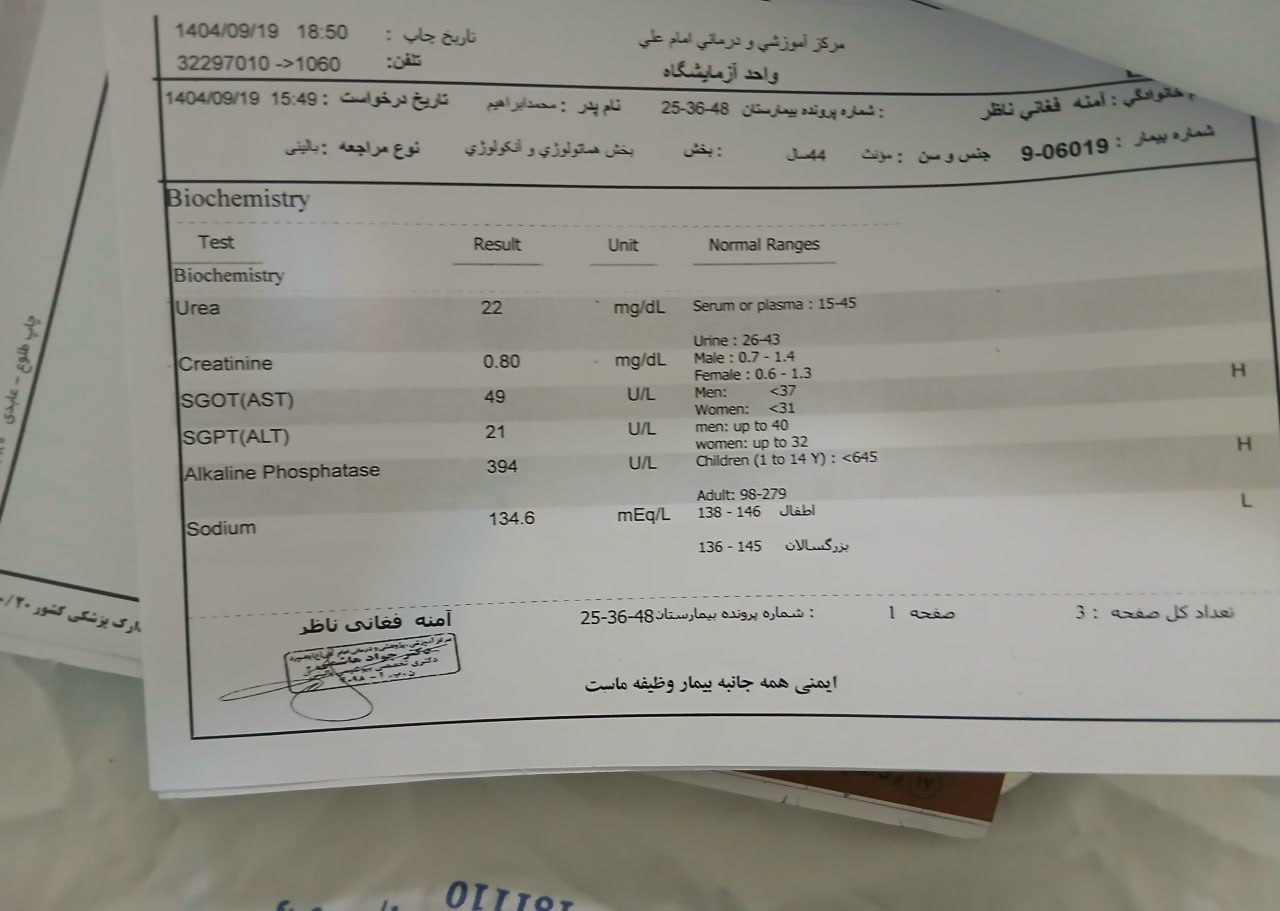

۱۹ آذر

۱۹ آذر

به ترتیب؛ روز ها: ۲۸ آذر, ۲۹ آذر, ۳۰ آذر, ۱ دی

۱ دی